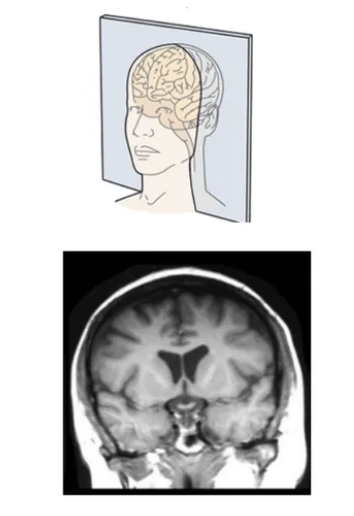

coronal plane

knowt flashcard image